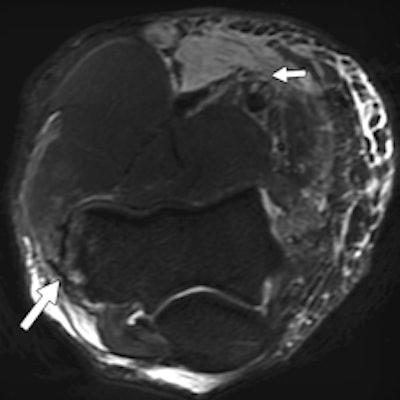

A 30-year-old male judo athlete with valgus stress and hyperextension injury of elbow. Top: Coronal proton density-weighted fat-saturated MRI shows full-thickness tear (white arrow) of proximal humeral attachment of anterior bundle of ulnar collateral ligament (UCL) and edema (black arrow) within surrounding muscle fibers. Below: Axial proton density-weighted fat-saturated MRI shows UCL posterior bundle disruption (long white arrow), with fluid surrounding ulnar nerve (short white arrow). However, ulnar nerve was contiguous on sequential images, with no transection. High-grade tear of flexor carpi ulnaris (black arrow) also was seen. Bottom: Axial proton density-weighted fat-saturated MRI shows high-grade tear of flexor digitorum superficialis (long arrow) and fluid surrounding median nerve (short arrow). All images reprinted with permission from the American Journal of Roentgenology.